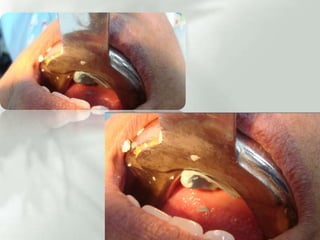

Plan de tratamientoFASE IDesprogramación muscular , terapia oclusal, (guarda oclusal) FASE IIOperatoria dental en dientes: AmalgamasResinasIncrustacionesPujanaGarcia Salmones JoseAgustin, Et, al, Oclusion tratado de teoria y practica para el odontologo  2009Martinez Ross Erik Et, Al, OclusionOrganica y  Ortognatodoncia,  2009PegoraroLuiz Fernando, Et al, Protesis Fija  2001

Plan de tratamientoFASEIDesprogramación muscular , terapia oclusal, (guarda oclusal) FASE IIOperatoria dental en dientes: AmalgamasResinasIncrustacionesPujanaGarcia Salmones JoseAgustin, Et, al, Oclusion tratado de teoria y practica para el odontologo 2009Martinez Ross Erik Et, Al, OclusionOrganica y Ortognatodoncia, 2009PegoraroLuiz Fernando, Et al, Protesis Fija 2001